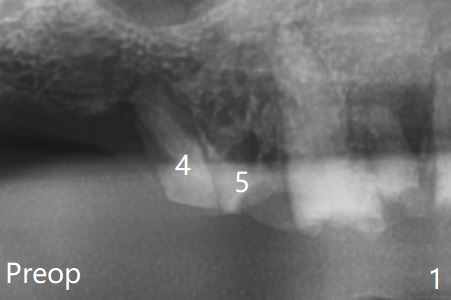

With use of BioXclude, the bone graft appears to remain in place 8 days postop (Fig.2,3).